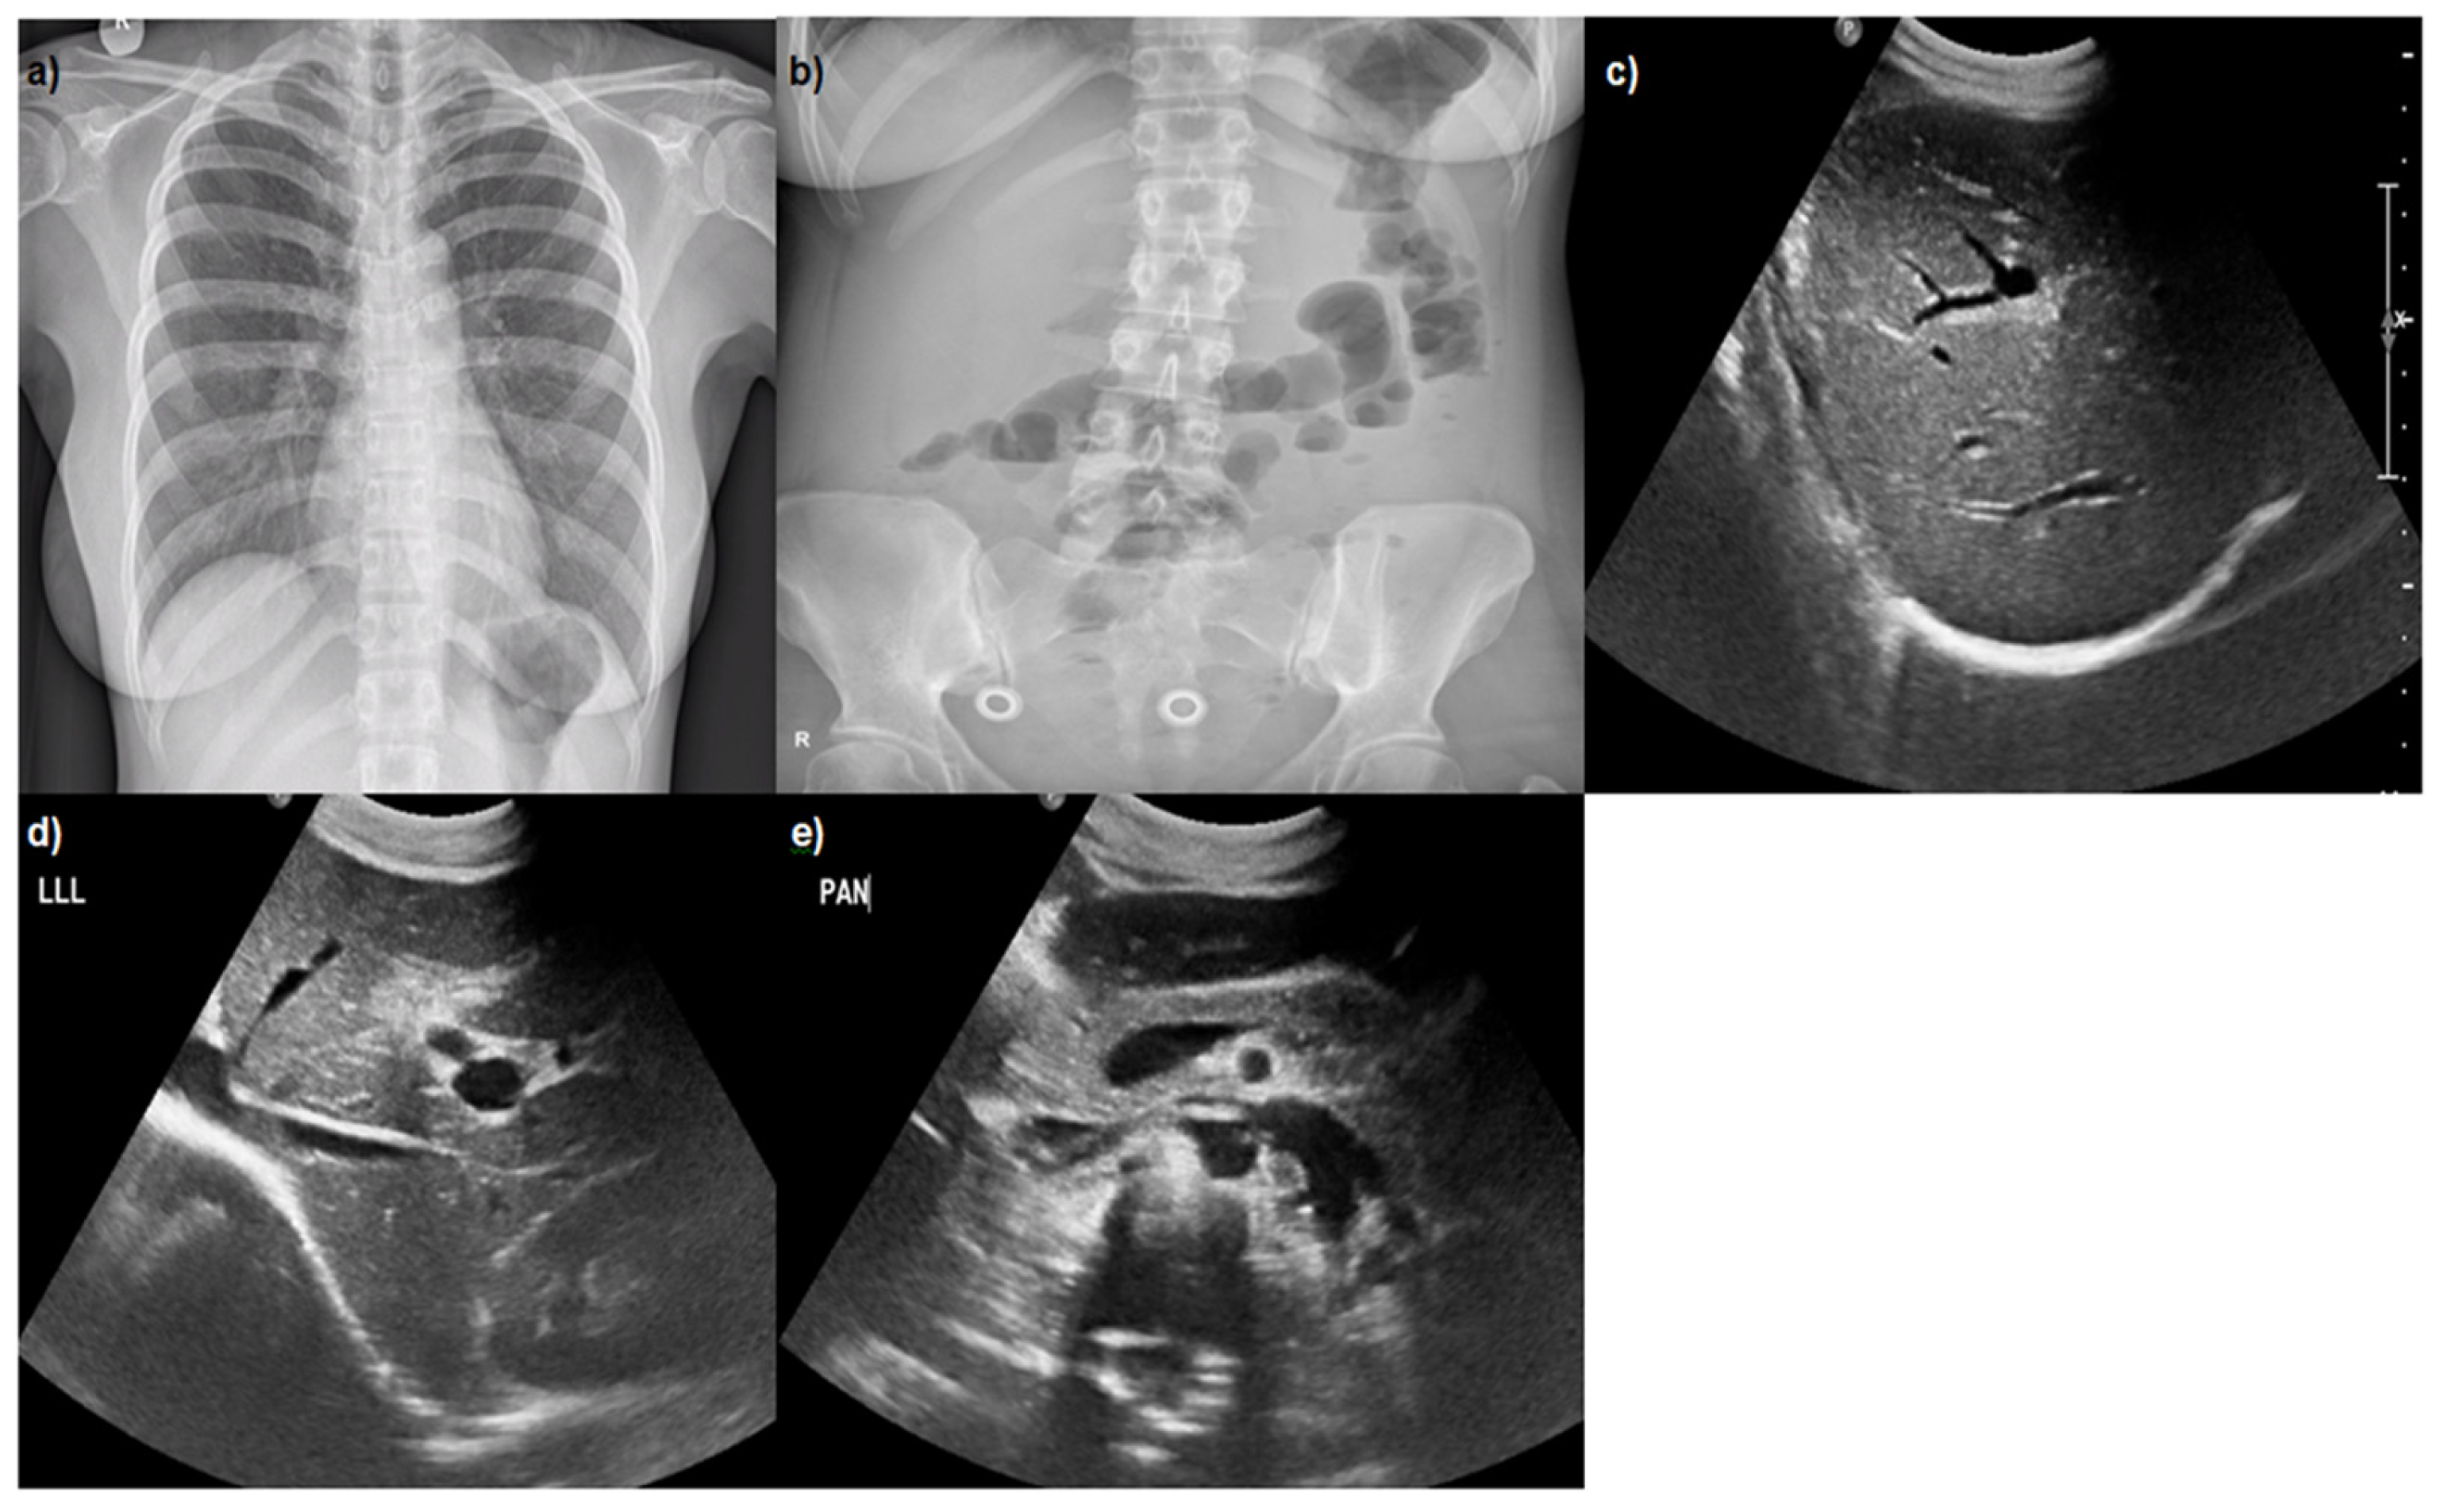

2. Case Presentation